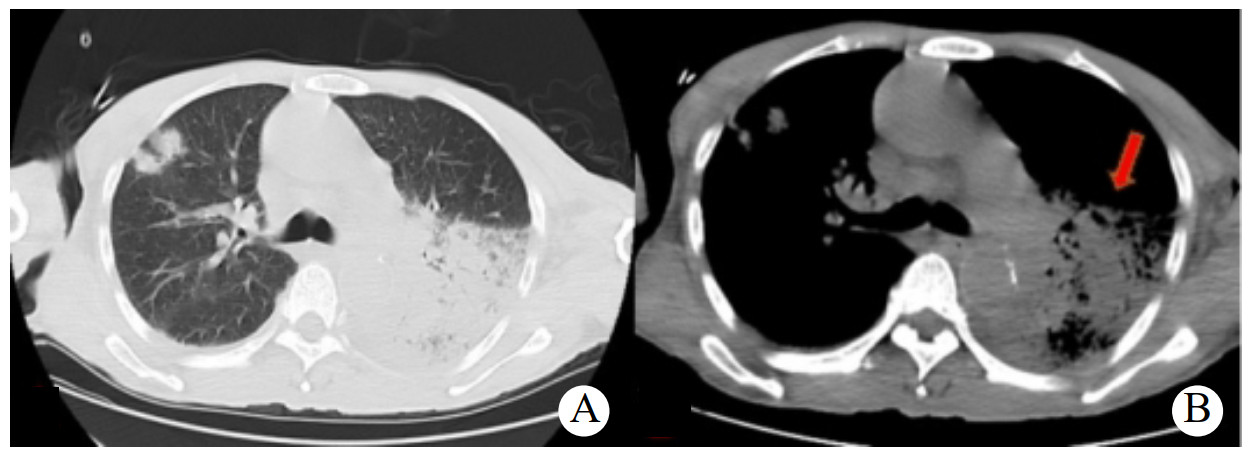

入科查体:体温39.2℃,心率107次/min,脉搏107次/min,血压98/67 mmHg,呼吸25次/min,血氧饱和度84%(未吸氧)。急性病容,精神软,双肺呼吸音粗,左肺呼吸音低,右肺可闻及湿啰音;心率不齐,心音不等,偶可闻及早搏。入院化验检查(2022-05-16):(1) 血气分析:酸碱度7.53,氧分压60.5 mmHg、二氧化碳分压33.6 mmHg、乳酸1.50 mmol/L;(2) 心肌酶和b型钠尿肽前体(Pro-BNP):Pro-BNP 12 653 pg/mL、乳酸脱氢酶785 U/L、肌钙蛋白-T 0.046 ng/mL、肌酸激酶101 U/L、肌酸激酶同工酶3 U/L;(3) 炎症指标:白介素-6 285.00 pg/mL、降钙素原1.55 ng/mL、肝素结合蛋白111.27 ng/mL、C-反应蛋白308.2 mg/L;(4) 肝肾功能:谷草转氨酶275 U/L、谷丙转氨酶124 U/L、δ-胆红素114.4 μmol/L、白蛋白31.2 g/L,肌酐67μmol/L;(5)血常规:白细胞计数10.5×109/L、血红蛋白120 g/L、中性粒细胞百分比95.7%;(6) 凝血功能:D-二聚体5610 μg/L、活化部分凝血活酶时间40.1 s、凝血酶原时间13.9 s。入科后进一步完善相关辅助检查。心电图示:窦性心律,左心室高电压,频发室性早搏,ST段、T波改变;床边心超示:全心增大,左心功能不全,主动脉瓣少-中等量反流,二尖瓣、三尖瓣少-中等量反流,少量心包积液,左心射血分数30%左右;胸部CT:两肺散在渗出,左肺大片实变,两侧少量胸腔积液(图 1)。

| 图 1 入院第1天胸部CT:A两肺渗出;B箭头所指大片实变 |